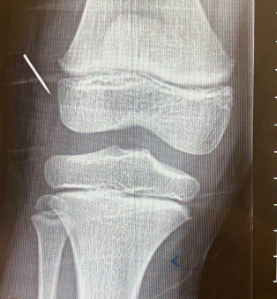

患儿8岁女孩,昨日下午领居家玩耍,不慎将针刺入体内,今早患儿出现右下肢疼痛,不能行走,与当地医院摄片检查,发现右侧膝关节外侧有一枚断针,建议来我院就诊!

我院儿外科明葛东副主任医师、戴文文主治医师和麻醉科赵新民副主任医师术前认真研讨,决定在B超准确定位下实施该手术,既可以避免患儿摄入过多射线,又可以避免膝关节断针周围重要血管及神经组织的损伤。术中B超定位,探及断针长1.5厘米,距离皮肤0.8厘米,B超监测下体表刺入注射器精准探及异物,穿刺针旁作1厘米小切口,迅速找到并顺利取出异物,手术顺利,创伤小,患儿目前恢复好。

术前摄片